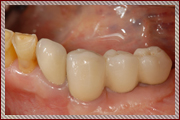

前歯のインプラント治療

前歯は周囲の骨が非常に薄いので抜歯後、時間の経過と共に歯茎は痩せて、骨も吸収して溶けてしまうことが多くあります

前歯のインプラント治療でとても重要なポイントは失った歯を回復してしっかり噛めるように機能を回復させることと、見た目が自然で人工物とわからないぐらいに綺麗にインプラント治療によって審美性を回復させることです。

しかし多くの場合、前歯の周囲の骨は非常に薄く、歯を失ったことになり顎の骨は吸収して痩せていき、それに伴って歯茎も下がってしまいます。

このままの状態でインプラント治療を行うと周りの歯と長さの違う不自然な被せ物(人工歯)になってしまい見栄えが悪く清掃性もよくありません。

新プラントプロで3次元的に分析を行い、インプラントを埋入する位置を決定し、サージガイドを作成します

そのため前歯のインプラント治療では、より正確な位置にインプラントを埋入することが求められ、インプラント周りの歯茎も自然な仕上がりになるようにインプラント周囲組織の骨や歯茎も回復をしてあげる必要があります。

コンピューターガイデッドインプラント治療 + 歯科用顕微鏡を用いたマイクロサージェリー 審美的に良好な結果が得られています

当院では、コンピューターガイデッド インプラント治療で正確な位置にインプラント手術を行い、そして前歯などの審美領域では顕微鏡を使用したマイクロサージェリー(顕微鏡下手術)を行うことで傷跡の目立ちにくい自然な仕上がりのインプラント治療を行っています。